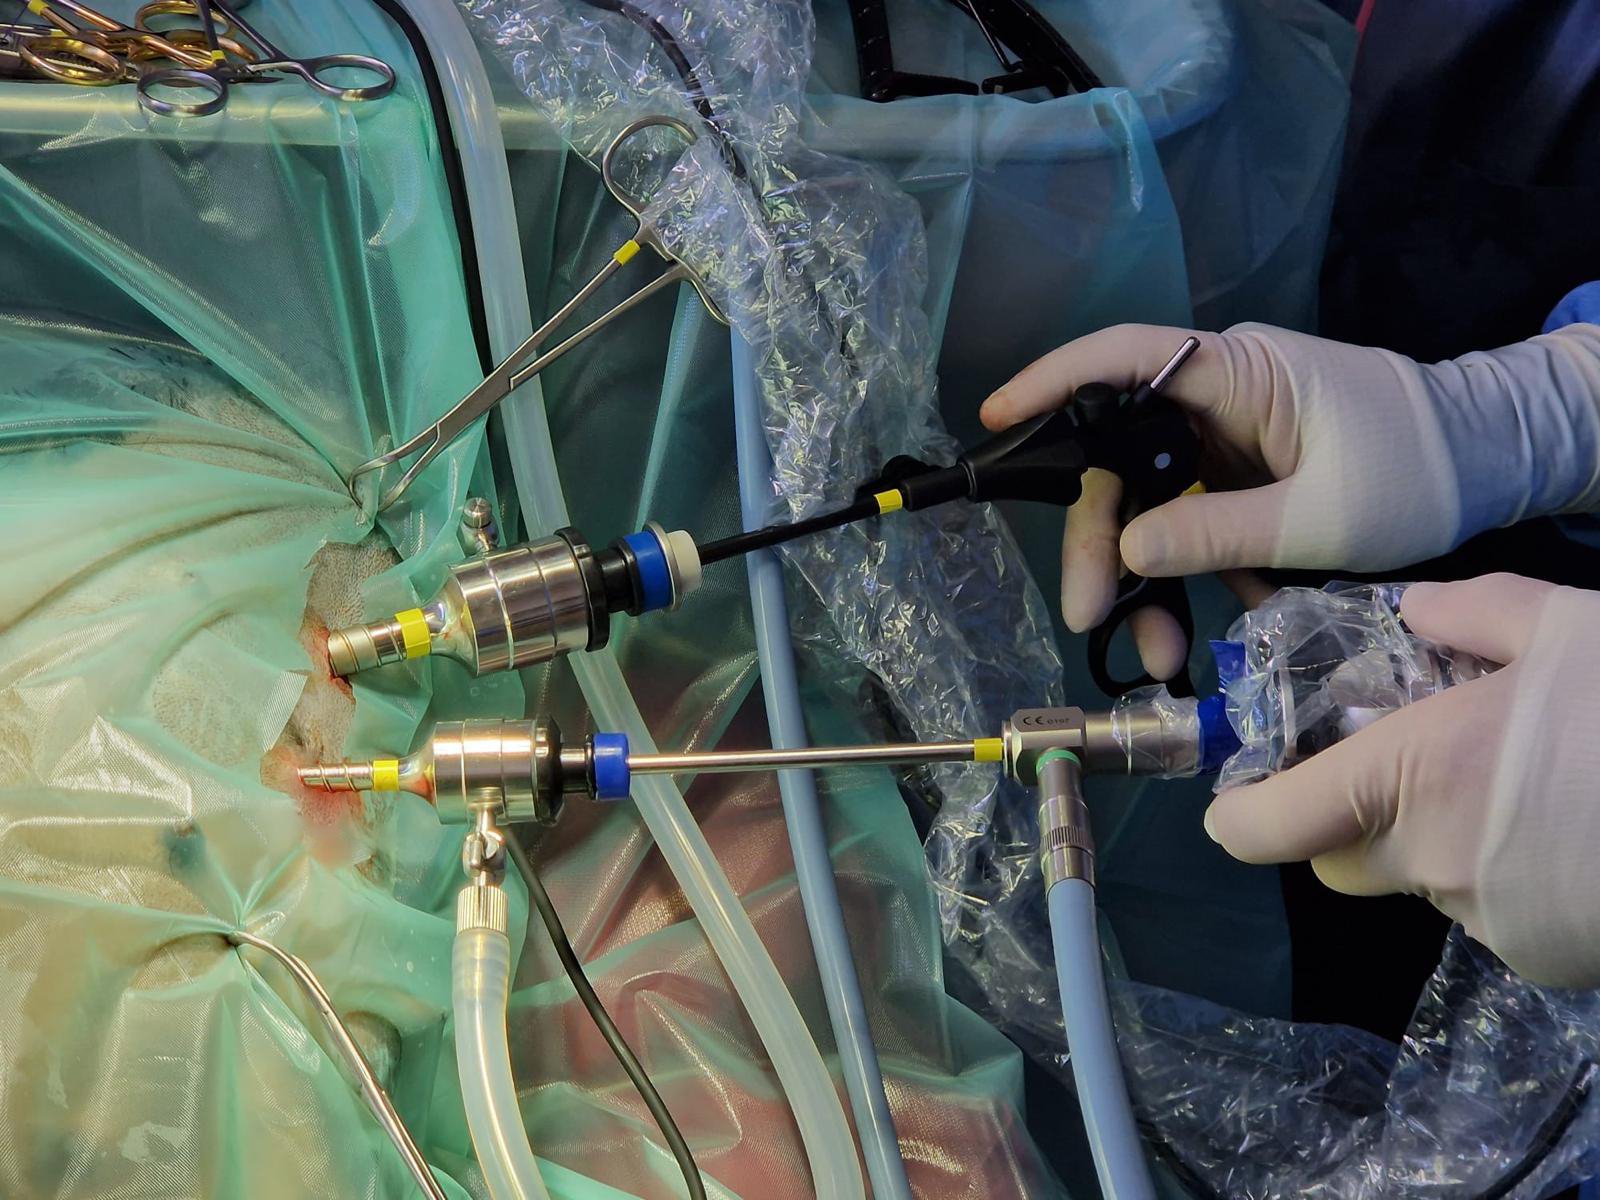

Keyhole Spay

Instruments used through small incisions to operate

Laparoscopy

Laparoscopy, or keyhole surgery, is increasingly used in veterinary medicine. Procedures performed include spay (ovariectomy), cryptorchid castrate, liver biopsy, laparoscopic assisted gastropexy. Smaller incisions mean less pain and quicker return to function.